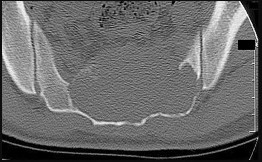

Figures 9a through 9d are the anteroposterior and lateral radiographs, CT scan, and technetium bone scan of a 12-year-old boy who has experienced 7 months of pain in his lower leg. The pain limits his ability to participate in sports and he is having difficulty sleeping. He is afebrile, and laboratory study findings including an erythrocyte sedimentation rate, C-reactive protein, and complete blood count are within normal limits.

CLINICAL SITUATION FOR QUESTIONS 9 THROUGH 11

The images and clinical history support a diagnosis of osteoid osteoma, which most commonly occurs in adolescence. Although these lesions can be seen in any bone, they are usually located in the femur and tibia. The significant inflammatory response to this tumor is secondary to high levels of prostaglandin production. Characteristic night pain is relieved with nonsteroidal anti-inflammatory drugs (NSAIDs) or by aspirin.

Radiographic images show thickened bone and a small central nidus. Thin-cut CT scan is the imaging of choice to visualize the nidus. A bone scan is associated with uptake but is not specific. Treatment options include expectant management with NSAIDs and observation under the premise that these lesions eventually burn out. Contemporary treatment involves RFA. Historically, these lesions were treated with en bloc resection; however, this technique has largely fallen out of favor because of the high efficacy and comparative low morbidity associated with RFA.

When an osteoid osteoma occurs in the spine, it is located in the posterior elements, and paraspinal pain and scoliosis often are present.